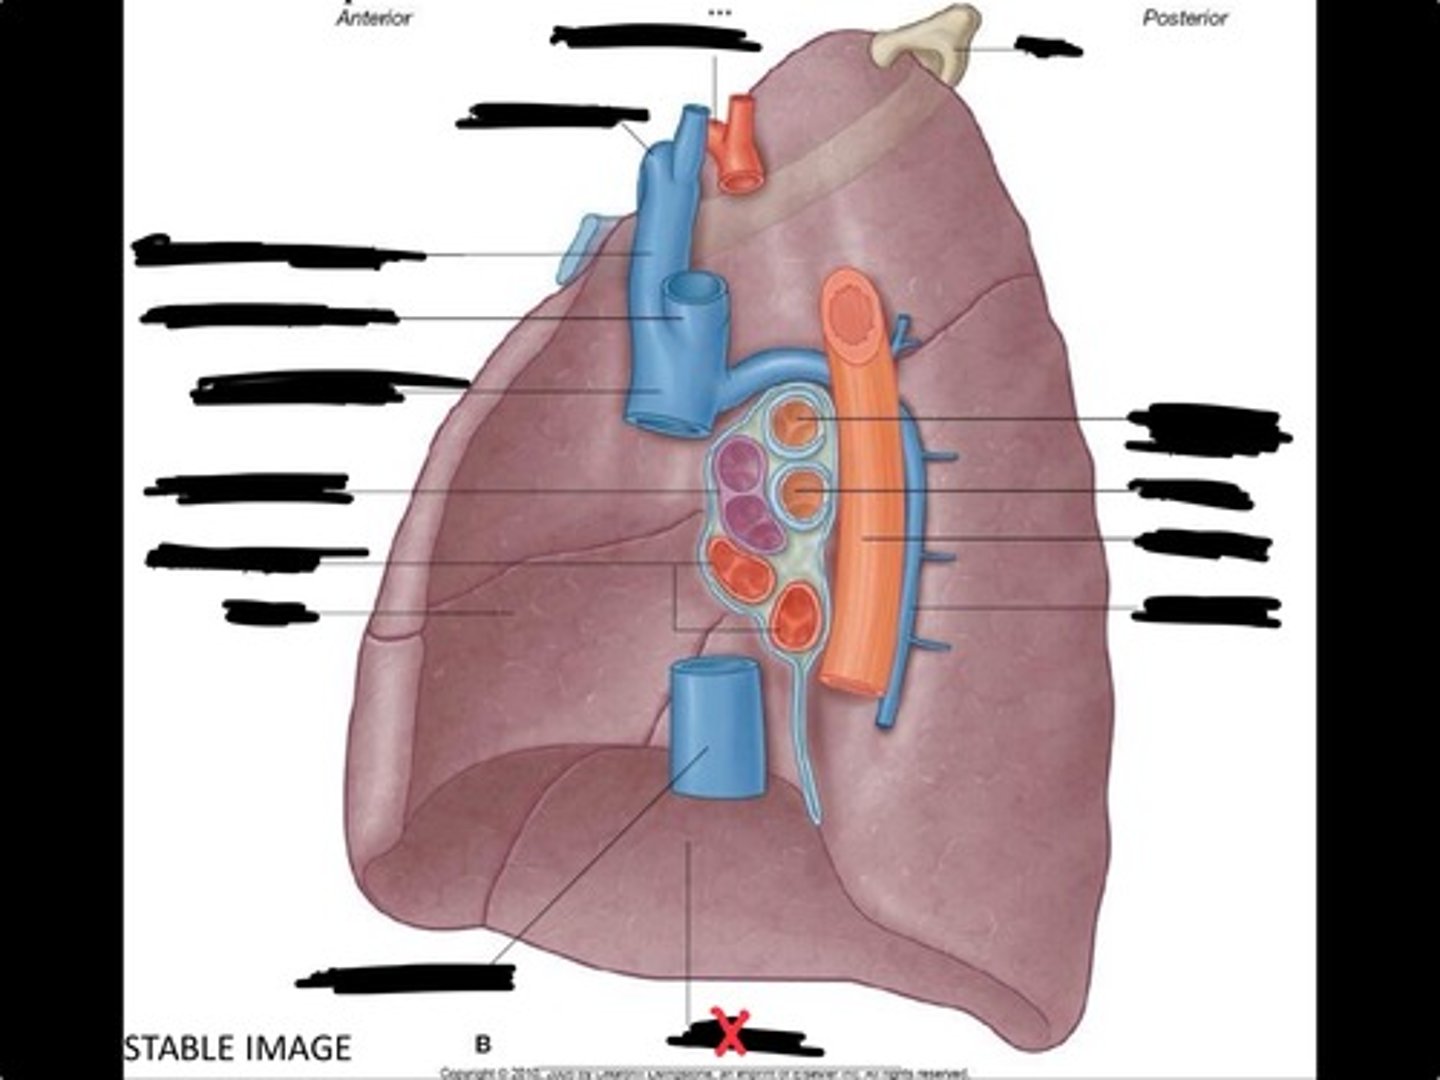

Inferior vena cava

Superior vena cava

Subclavian vein

Right bracheocephalic vein

Subclavian artery

Esophagus

Bronchus

Rib 1

Left subclavian artery

Left brachiocephalic vein

Aortic arch

Pulmonary artery

Pulmonary vein

Heart

Left brachiocephalic vein

Azygos vein

Esophagus

Bronchus